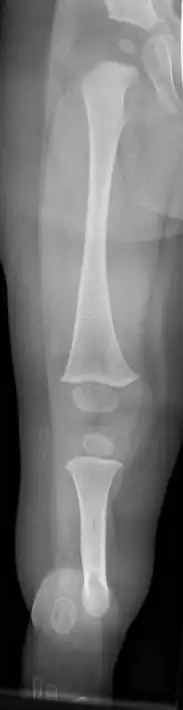

X-ray image of fibular hemimelia type II (fibula completely absent)

Fibular hemimelia or longitudinal fibular deficiency is "the congenital absence of the fibula and it is the most common congenital absence of long bone of the extremities."[1][2] It is the shortening of the fibula at birth, or the complete lack thereof. Fibular hemimelia often causes severe knee instability due to deficiencies of the ligaments. Severe forms of fibula hemimelia can result in a malformed ankle with limited motion and stability. Fusion or absence of two or more toes are also common.[3] In humans, the disorder can be noted by ultrasound in utero to prepare for amputation after birth or complex bone-lengthening surgery. The amputation usually occurs at six months with removal of portions of the legs to prepare them for prosthetic use. The other treatments, which include repeated corrective osteotomies and leg-lengthening surgery (Ilizarov apparatus), are costly and associated with residual deformity.[4]

Characteristics are:

• A fibrous band instead of the fibula

• Short deformed leg

• Absence of the lateral part of the ankle joint (due to absence of the distal end of the fibula), and what is left is unstable; the foot has an equinovalgus deformity

• Possible absence of part of the foot requiring surgical intervention to bring the foot into normal function, or amputation.

• Possible absence of one or two toes on the foot

• Possible conjoined toes or metatarsals